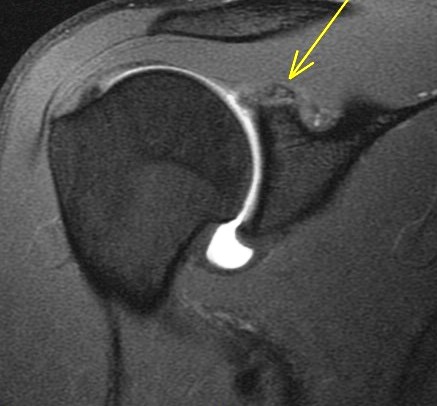

19 y/o college pitcher. Pain with throwing.

Posterior superior glenoid bone build up from chronic peel back stress. There are superimposed acute edematous changes. Abstract from Burkarts article describing it is included. Reference article.

Posterior Peel Back Lesion of Internal Impingement